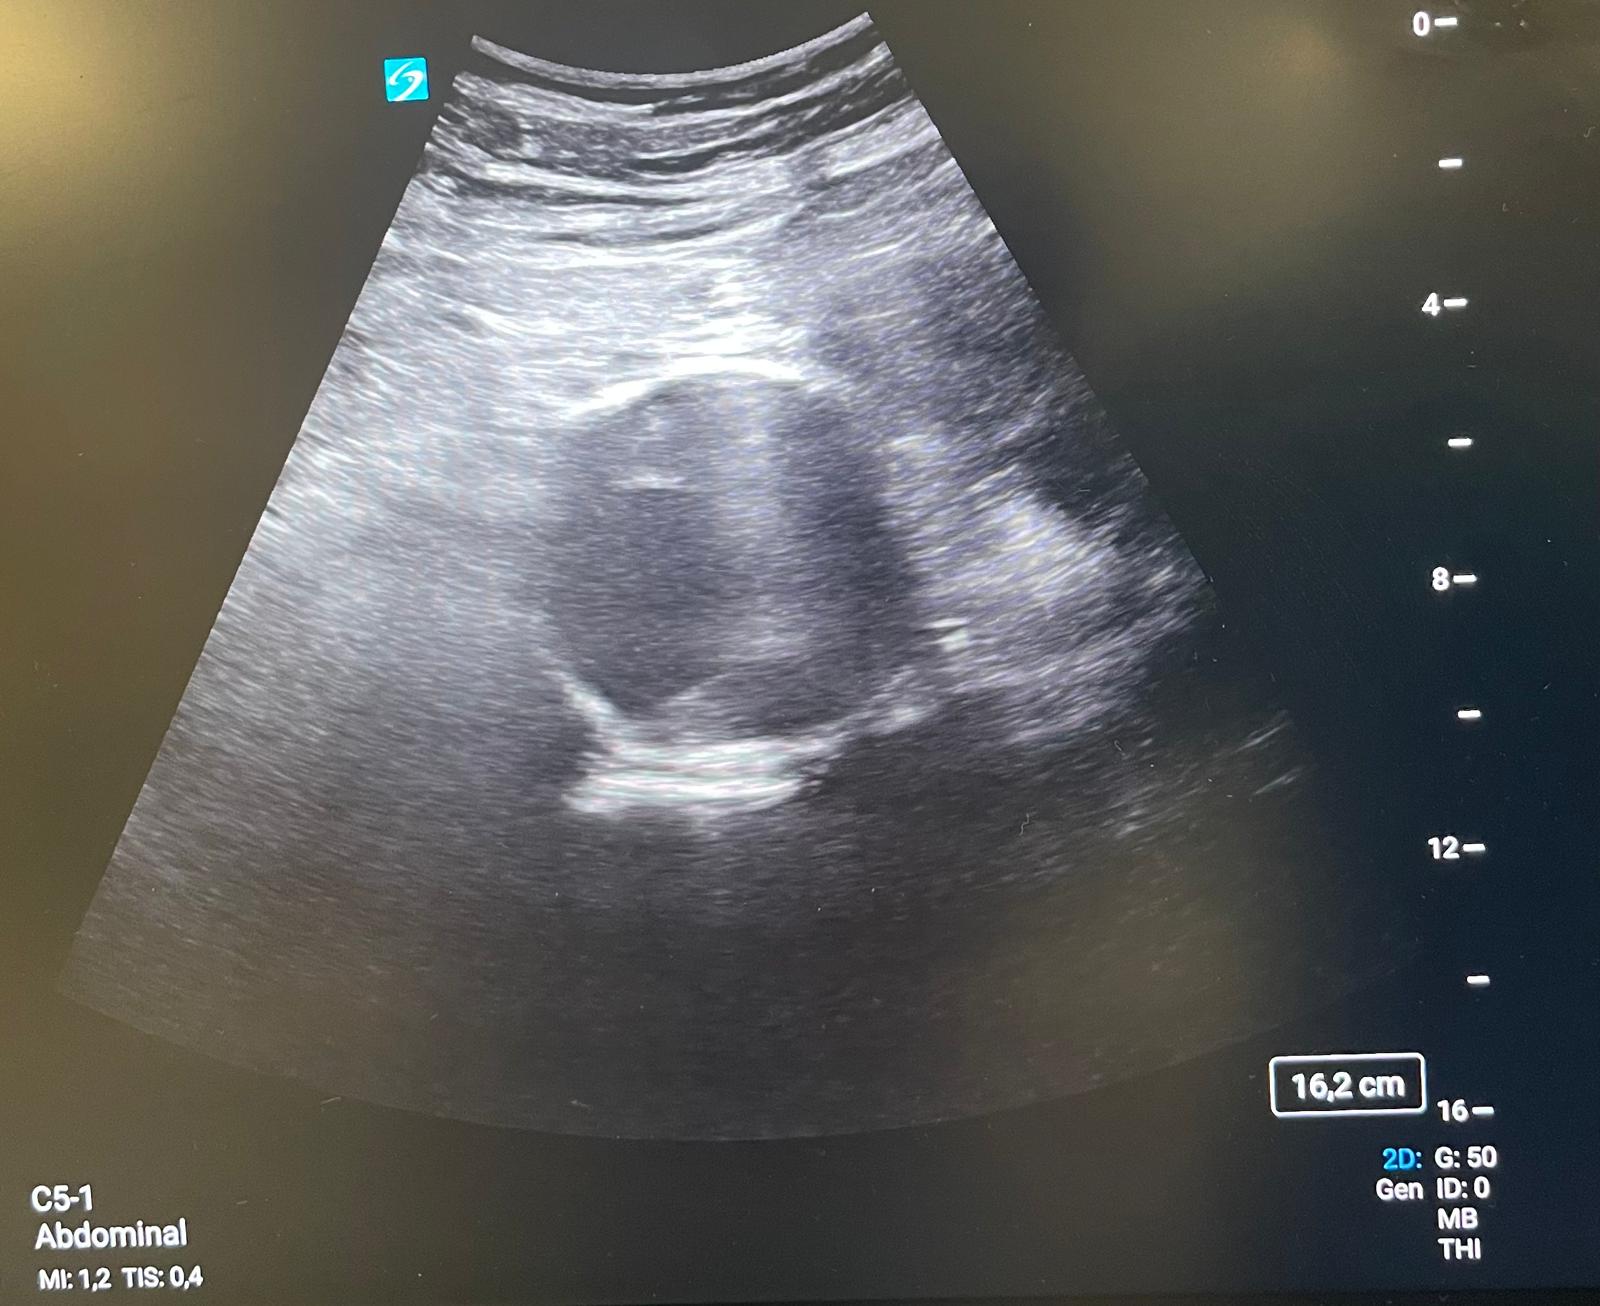

Se mantiene en la sala de reanimación de Urgencias, estable, pero con tendencia a la hipotensión y glasgow 15, para valoración por UMI y Cardiología. Tomo la iniciativa para realizar ecografía clínica para valoración de ventana cardiaca, pulmonar y grandes vasos como despistaje de “5H y 5T”.

Al valorar grandes vasos encuentro una imagen compatible con aneurisma de aorta abdominal (AAA) de 6,3 cm de diámetro con trombosis del 50% de su luz, no diagnosticado previamente. Se confirma el hallazgo en mediante TC, sin presencia de patología aórtica aguda.